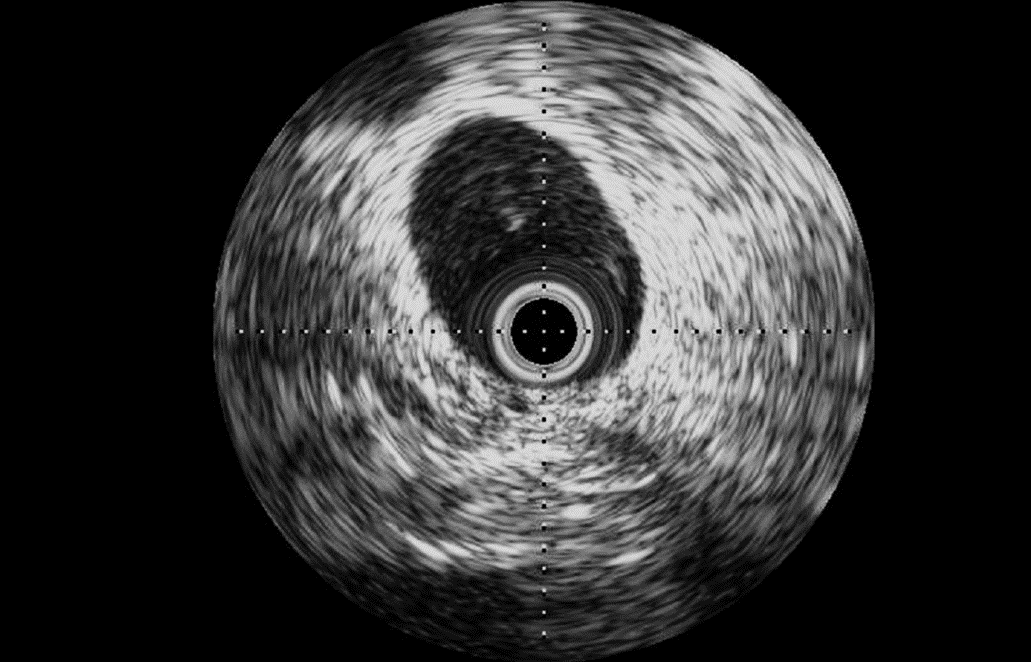

Intravascular ultrasound (IVUS): external iliac vein of a 100 kg-male ovine

• Intravascular ultrasound (IVUS) may be a valuable tool to evaluate vessel morphology and size before implantation, guide device implantation, and assess long-term device position and safety.

• A complementary technique, optical coherence tomography (OCT) is an imaging modality that uses near-infrared light to provide high-definition images with higher spatial resolution and tissue penetration than IVUS, and our imaging specialists can help determine which technology is best for your needs.